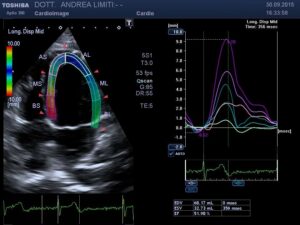

L’ecocardiografia è una metodica nella quale gli ultrasuoni sono utilizzati per visualizzare l’interno del cuore ed il flusso del sangue attraverso le valvole. A differenza delle radiazioni utilizzate in radiologia, gli ultrasuoni sono innocui, per cui non è necessaria alcuna precauzione e l’esame può essere eseguito su qualunque paziente innumerevoli volte (anche nelle donne in gravidanza).

Durante l’esame la sonda viene appoggiata al torace del paziente e gli ultrasuoni vengono diretti all’interno del corpo, senza che il paziente possa avvertirli. Gli ultrasuoni arrivano al cuore e ritornano alla sonda generando echi che sono utilizzati per visualizzare sullo schermo un cuore “virtuale” che ci informa del comportamento del cuore reale del paziente. Le onde sonore possono essere riflesse anche dal sangue in movimento all’interno del cuore e fornire informazioni sul flusso all’interno del cuore e dei vasi.

La visita cardiologica, l’Elettrocardiogramma e l’Ecocardiogramma bidimensionale Color Doppler transtoracico consentono di acquisire una ricchezza di informazioni sullo stato anatomico e funzionale del cuore di livello molto elevato che spesso consentono un primo accurato inquadramento dei problemi cardiologici del paziente. E’ importante tuttavia sapere che, anche con gli apparecchi più avanzati, l’ecocardiografia non offre una valutazione diretta dello stato delle coronarie e quindi l’esame non può essere discriminante per la valutazione di sospetti dolori cardiaci.